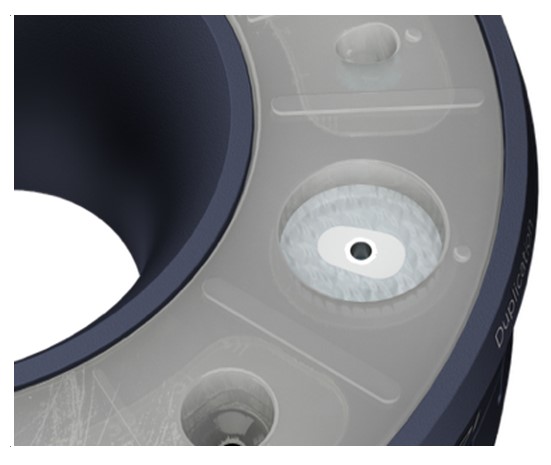

Matrița sistemului (Cervico Mold) este utilizată pentru fabricarea bonturilor de vindecare Cervico și a posturilor de amprentă (seamănă cu profilul cervical al protezei implantare dorite). Toate părțile funcționale ale matriței (bază, inserție din silicon) pot fi refolosite după o dezinfecție adecvată și un proces de sterilizare, urmând aceleași standarde ca și în cazul procesului de sterilizare a instrumentelor dentare refolosibile.

Rotește inelul superior al matriței până când forma/ dimensiunea dorită a puțului de silicon este aliniată la inserția protetică VPI dorită, prezentă în baza matriței.

Rotește inelul superior al matriței până când puțul de dublare este aliniat la insertul de conexiune protetică VPI dorit prezent la baza matriței.

Aplică un agent lubrifiant pe pereții interiori ai puțului de dublare.